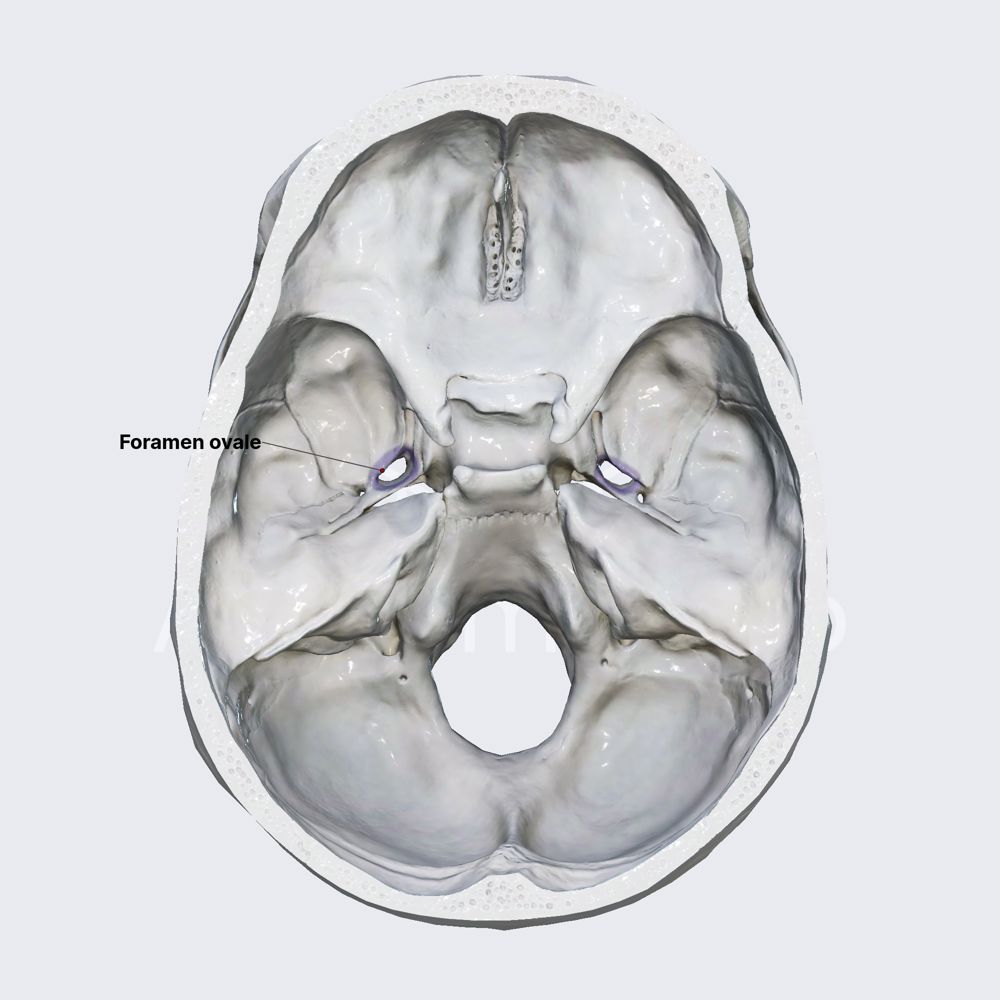

- Skull openings (overview)

- Foramen ovale